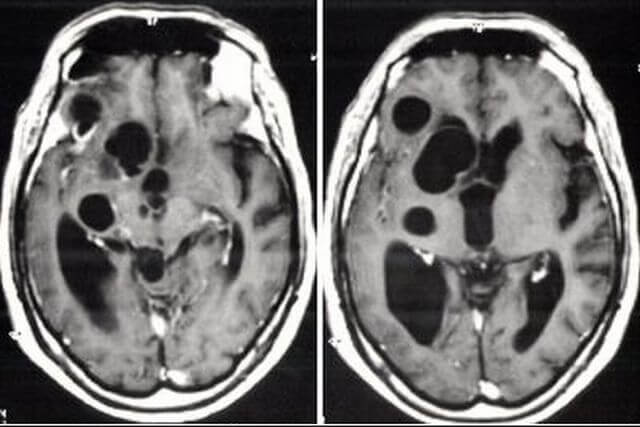

Как выглядят арахноидальная и ретроцеребеллярная кисты.